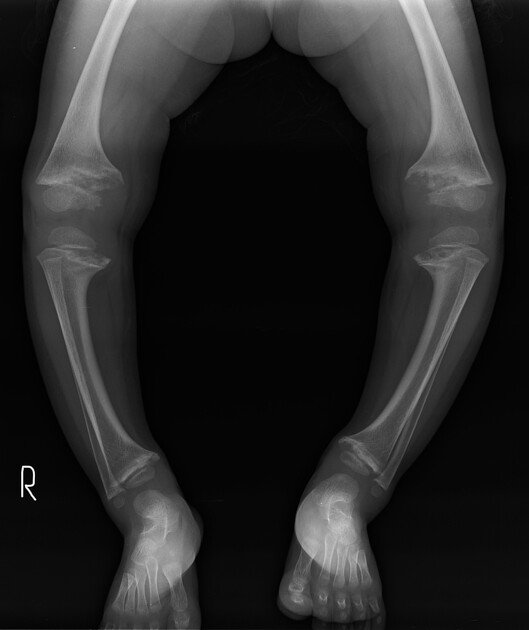

• Genu varum (bow leg): genu valgum (knock knee)

6. X-ray of knee, ankle, wrist: Cupping, fraying and widening of the distal ends of the long bone with generalized rarefaction.